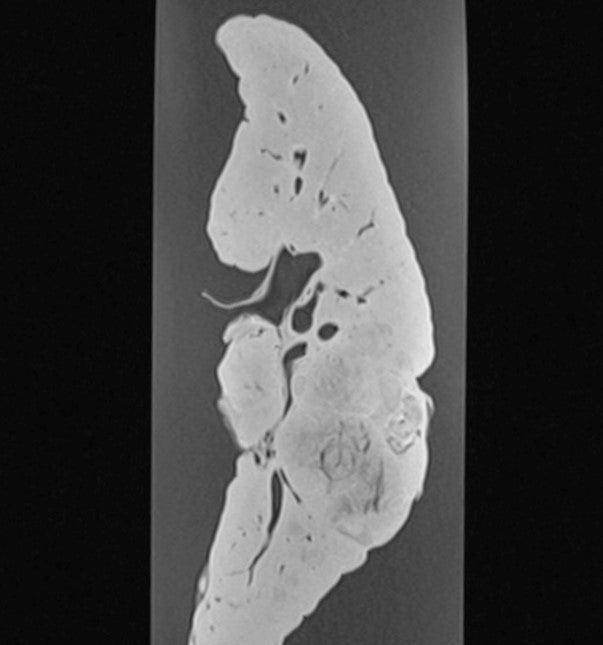

Kidney - Papillary Transitional Cell Carcinoma